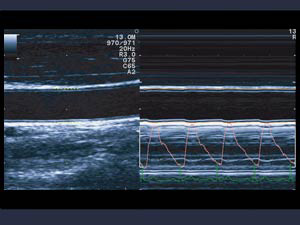

Кардиологи из 13 европейских центров принимают участие в этом проекте. На сегодняшний день проанализированы результаты исследований сонных артерий технологией eTRACKING компании Hitachi Aloka Medical с использованием ультразвукого датчика для сосудистых исследований более чем у 2 000 пациентов.

Подобные ультразвуковые технологии существую у все ведущих производителей ультразвуковых аппаратов, так например в компании Esaote - RFQIMT & RFQAS, GE – измерение комплекса IMT/AS.

Фото 1; 2 Ультразвуковые технологии компаний Hitachi Aloka Medical и Esaote измерения комплекса интима-медиа и ригидности аорты